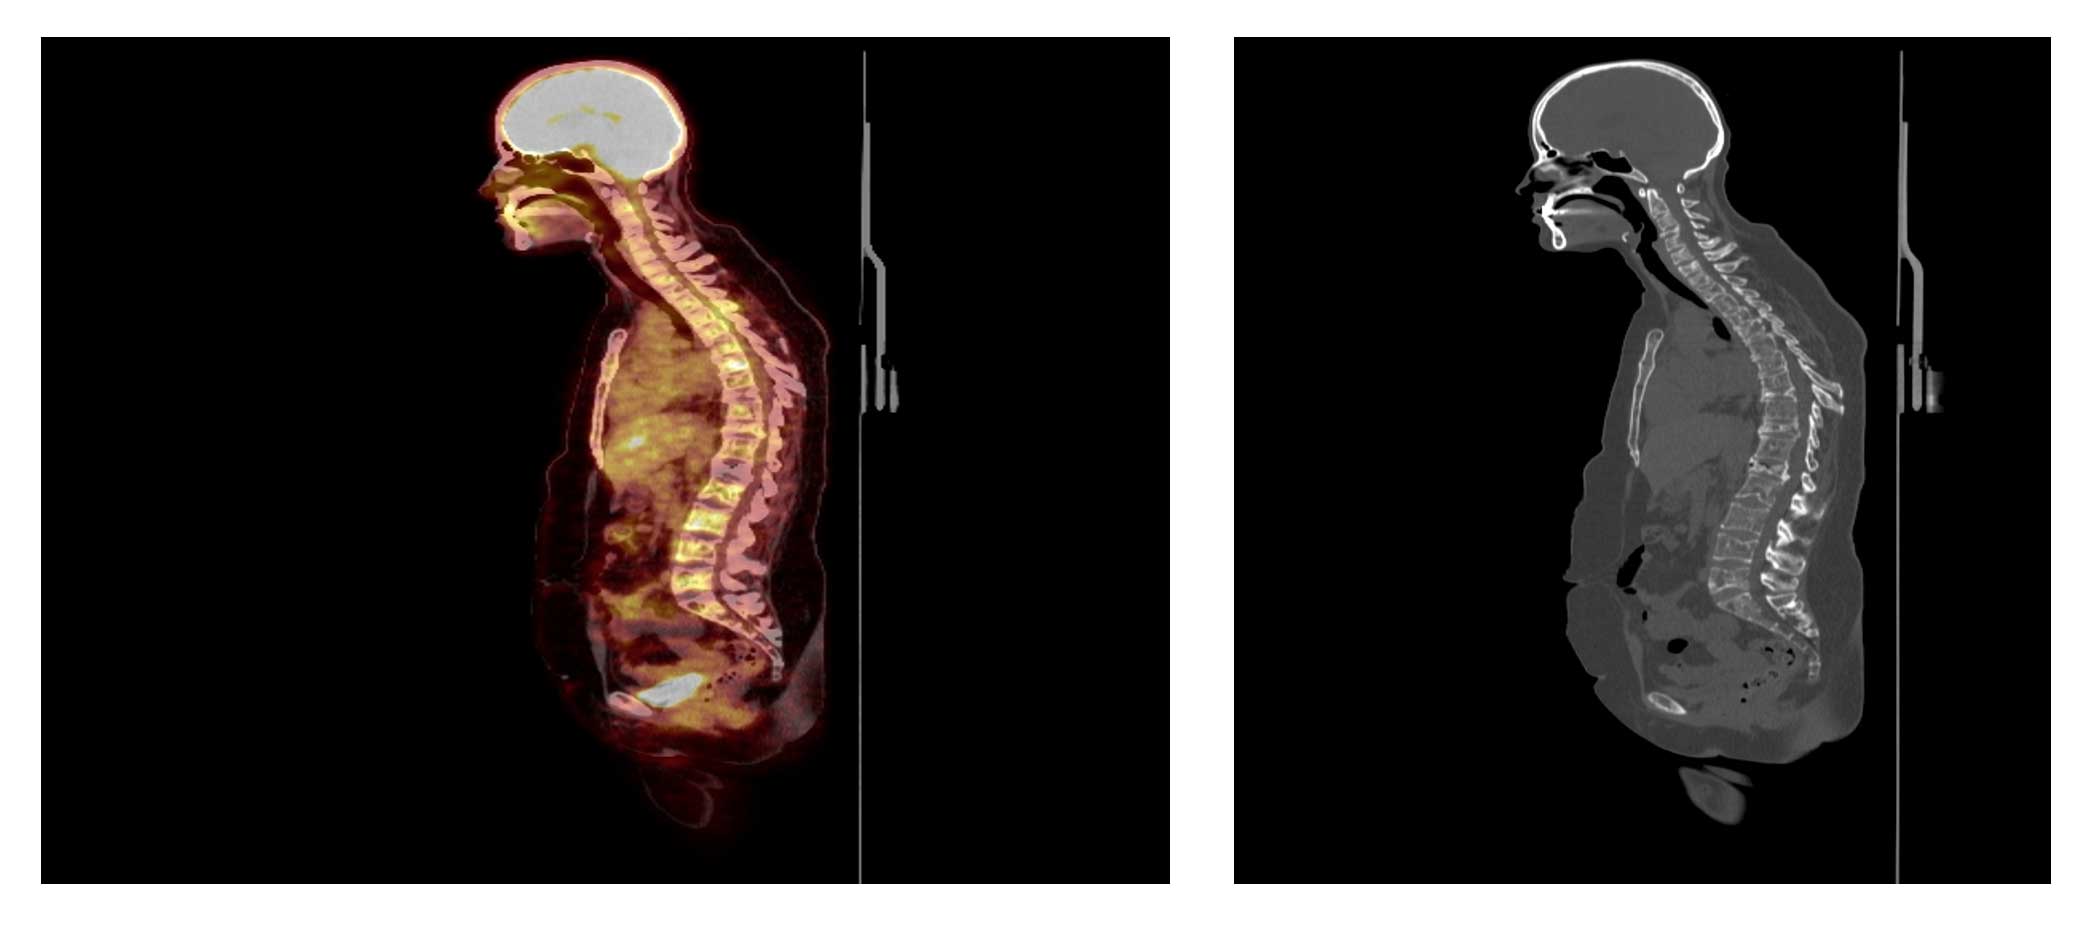

Ameliyat Öncesi: PET-CT’de çoklu metastazlar ve çökme kırıkları görülmekte.